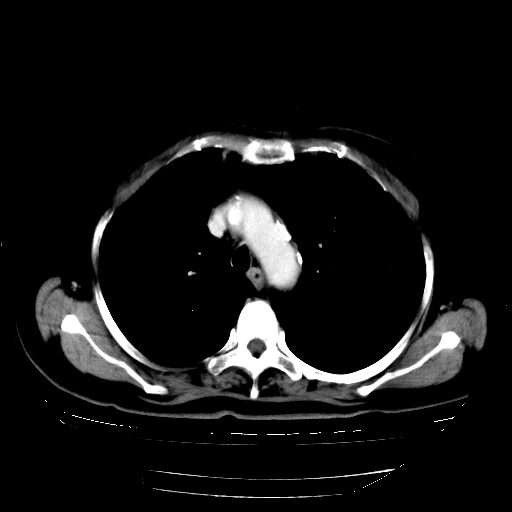

2.胸主动脉夹层。

支持,首先一元论解释。胸主动脉部分层面环形低密度,中心强化。环形影不强化。不象真假腔的改变。我考虑动脉炎,不太支持夹层动脉瘤-和大家的观点不一致,希望楼主让患者再做个心血管的彩超吧。

继发型肺结核,右下肺支气管内膜结核.右侧少量胸腔积液.主动脉夹层.